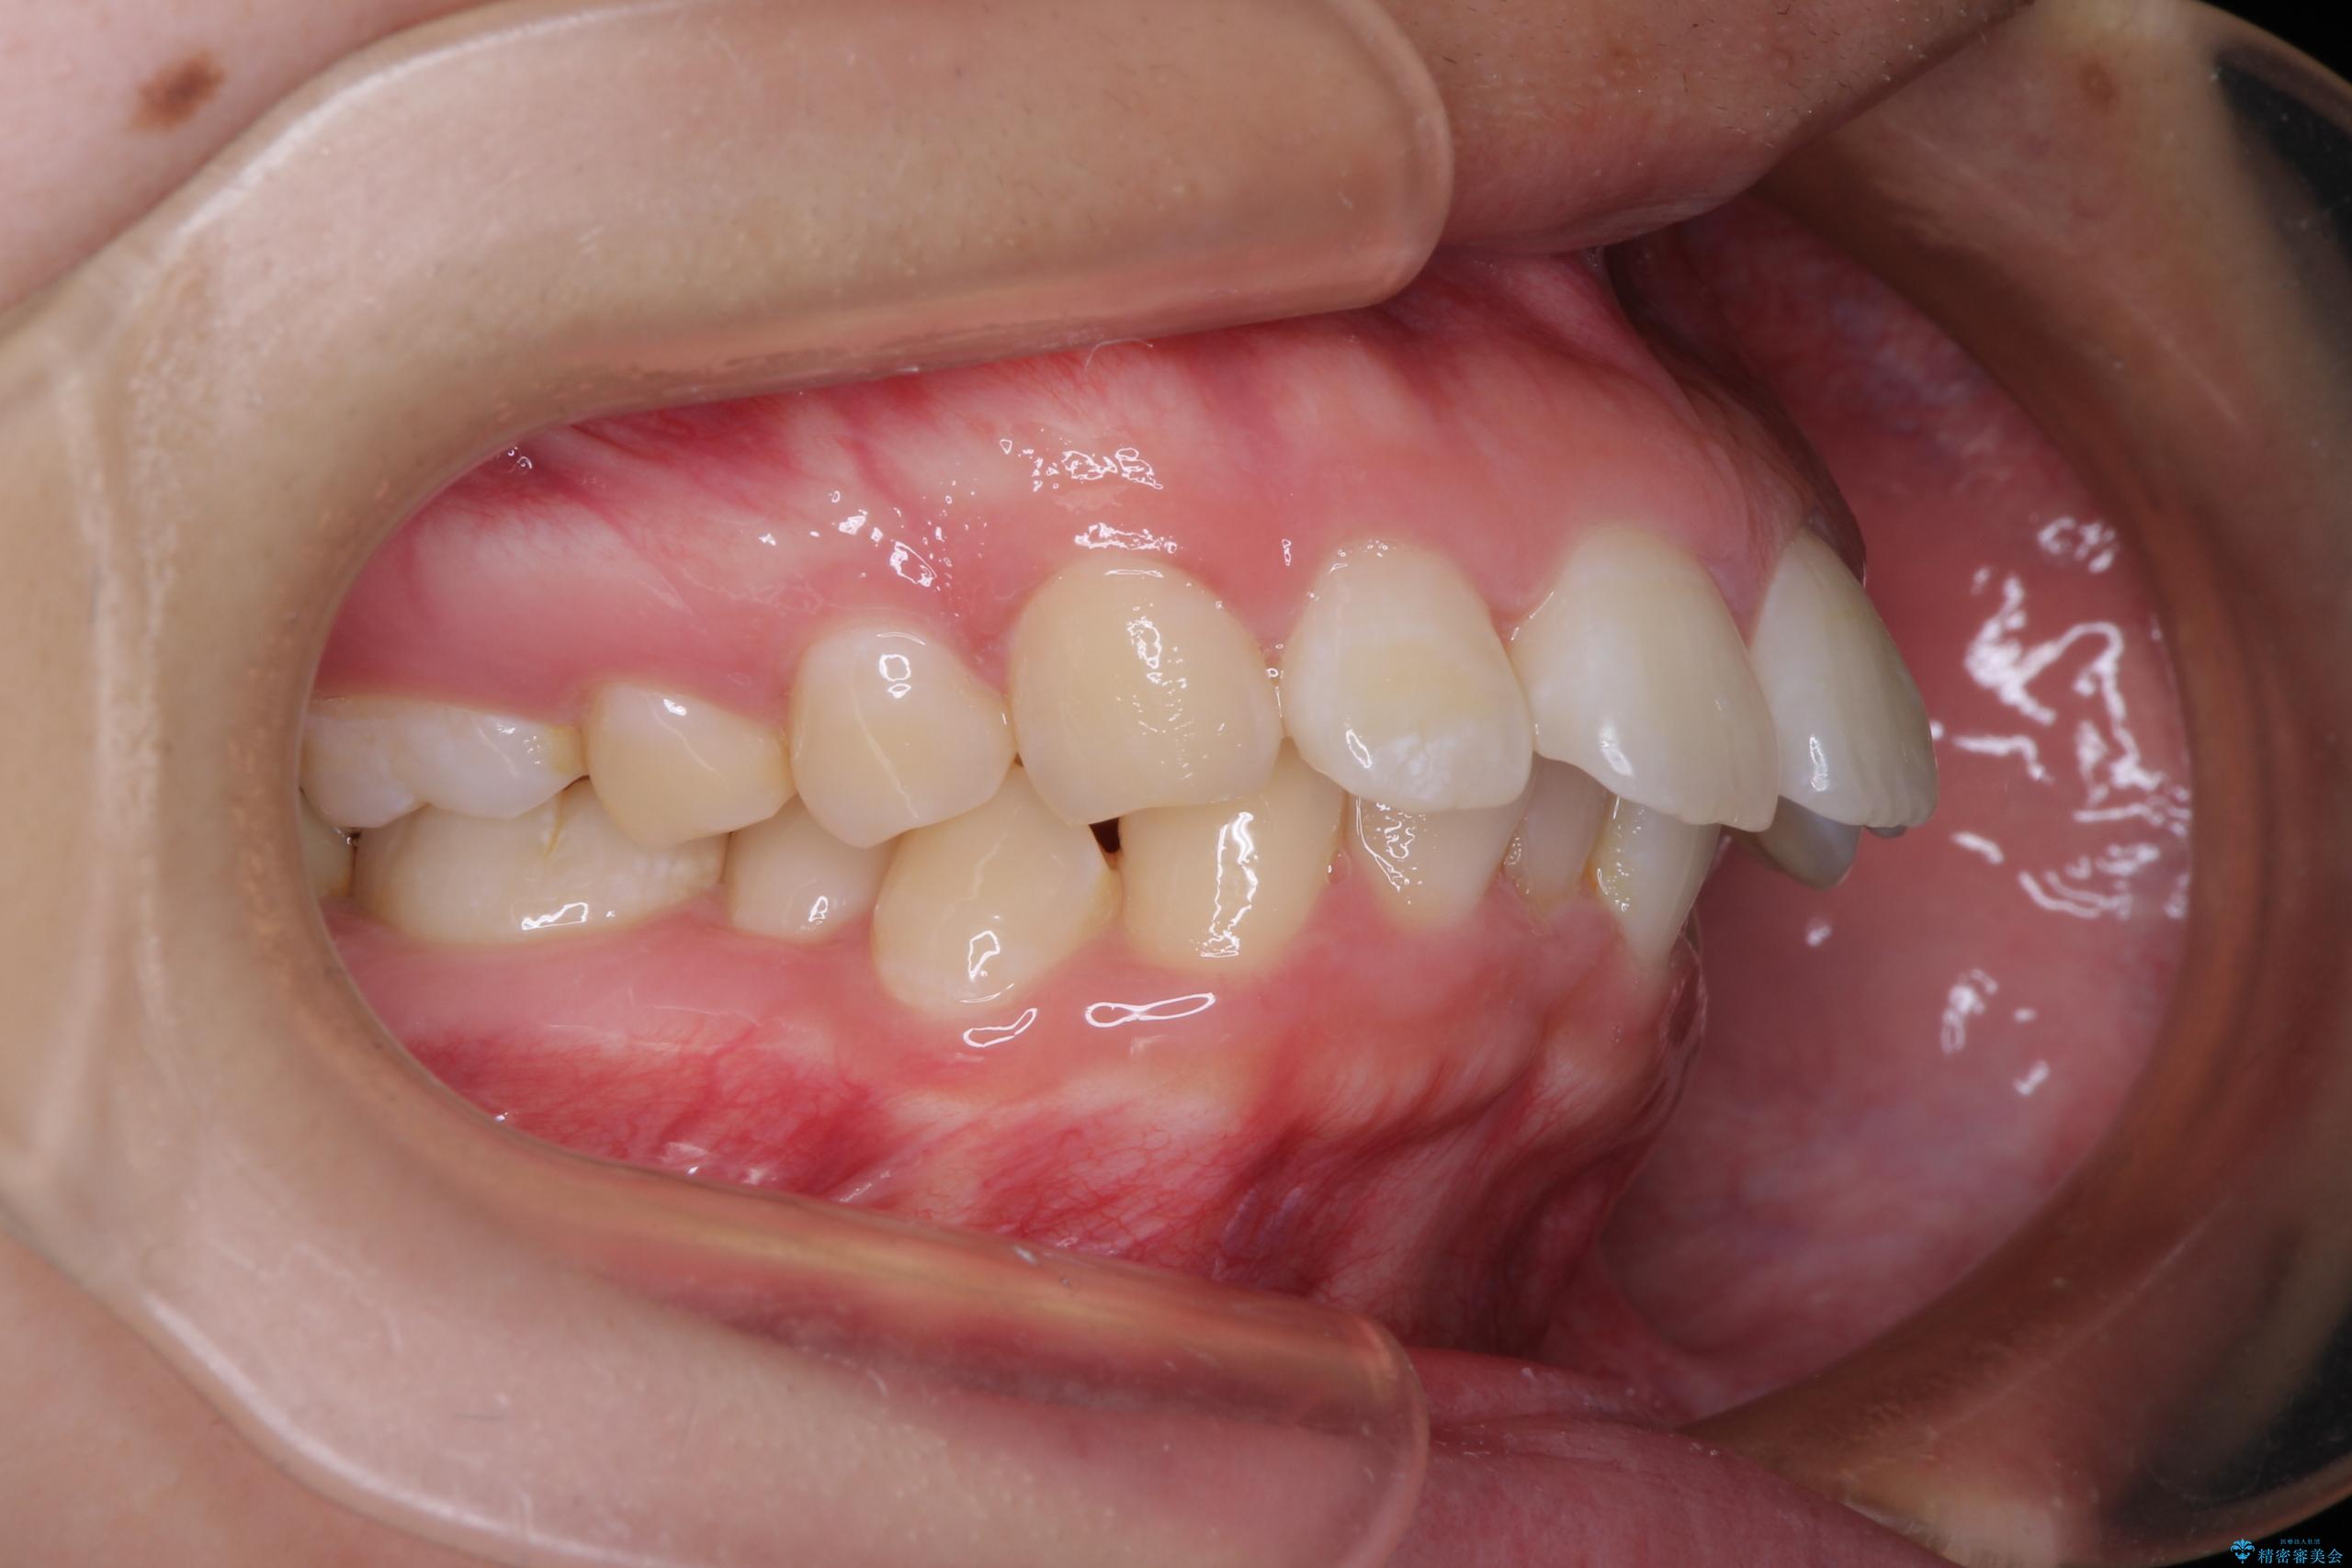

- 上顎前歯が飛び出していて唇がうまく閉じられないとのことで来院された患者様です。

くちばしのように前歯が突出していたため、口元を積極的に引っ込めるために、上下左右の小臼歯4本を抜歯することとしました。

また、上顎歯列が下顎に対して前方位に位置していたため、補助装置を用いて上顎歯列を後方に移動させ、より積極的に口元を下げるようにしました。

上下正中位置を改善するため、左下はイレギュラーに第二小臼歯を抜歯しました。そのため治療期間の長期化が予想されましたが、2年半ほどで期待通りの歯列に仕上げることができました。